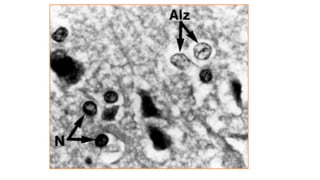

“Alzheimer type II astrocytosis”

• Pale, enlarged nuclei

• characterisic of HE

• Astrocyte (glialcell) volume is controlled by intracellular organic osmolyte which is glutamine • Increase glutamine levels in the brain result in increase volume of fluid within astrocytes resulting in cerebral edema (enlarged glial cells) • Neurological impairment “Alzheimer type II astrocytosis” • Pale, enlarged nuclei • characterisic of HE Increase Permeability of Blood-Brain Barrier